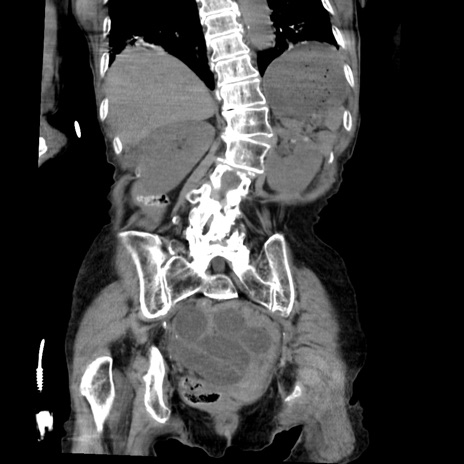

症例27(冠状断像)

【症例】80歳代女性

【主訴】嘔吐、腹痛

【現病歴】数時間前より嘔吐あり。心窩部痛出現し、徐々に右下腹痛あり。その後も数回嘔吐あり救急搬送となる。

【既往歴】左大腿骨頚部骨折手術

【身体所見】腹部は膨隆しているが軟らかく圧痛なし。腸雑音はやや亢進。

【データ】WBC 12000、CRP 19.05